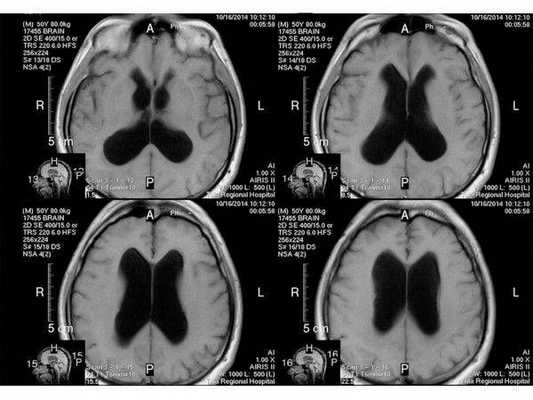

- МРТ в динамике показывает постепенное сужение желудочковой системы на 2 мм. Для сравнения представлены снимки МРТ от 14.05.2013 и от 16.10.2014.